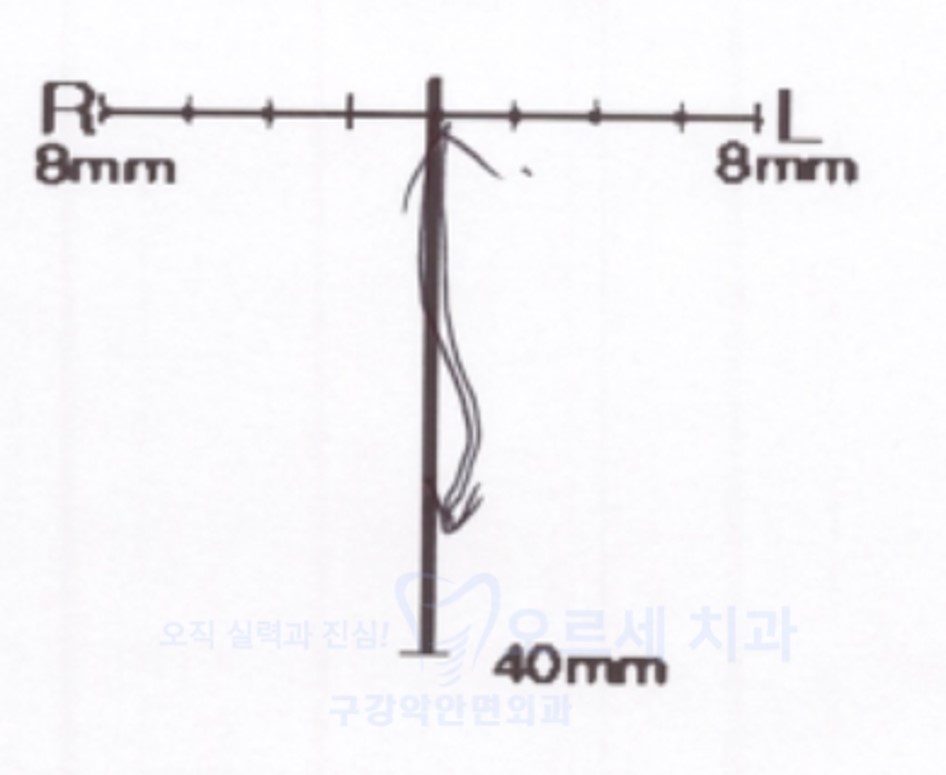

검사 결과 턱관절 내부 디스크 이상으로 턱 걸림 증상이 빈발했던 것으로 확인되었고요. 치아 마모 등의 이갈이 문제가 동반된 상태여서 턱관절 스플린트를 수개월간 착용하기로 계획하였습니다.